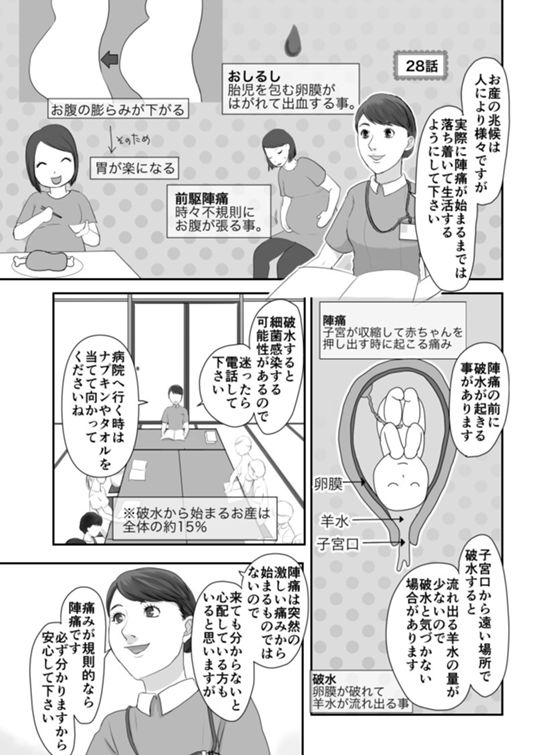

28話 出産の勉強

40話 おしるしと陣痛